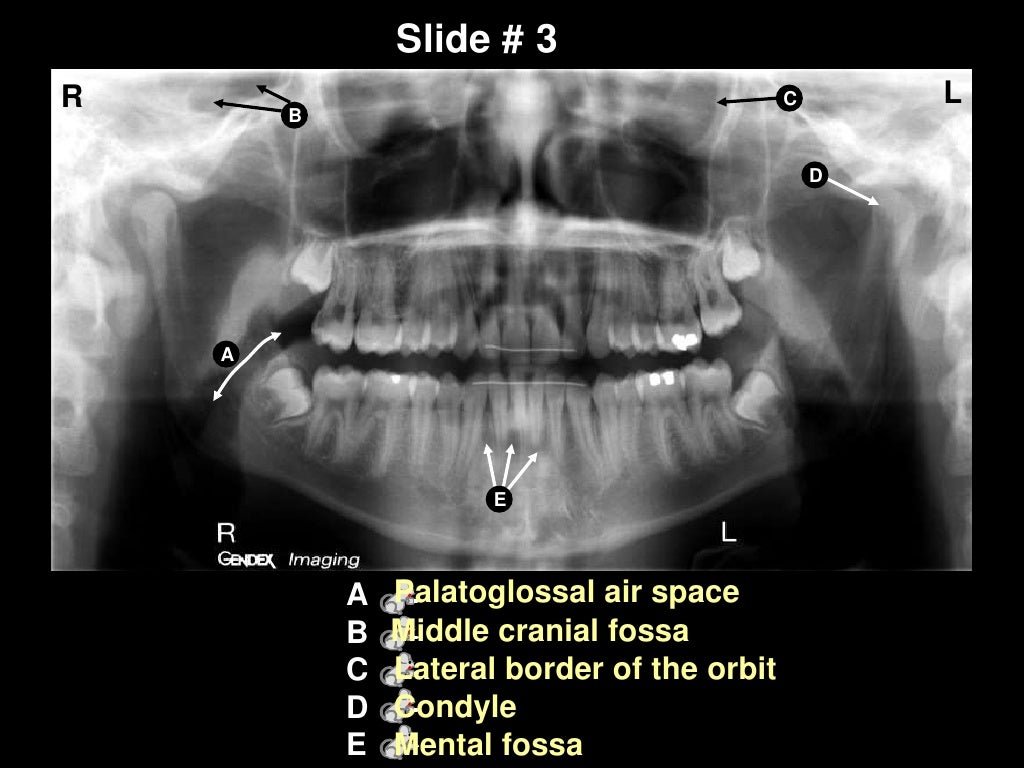

Panoramic Anatomy Quiz - By michaelvcook

Self study-pan-anatomy. Of course all the above frequency recommendations can be modified depending. 12.3 a dental panoramic radiograph depicting a curved tomographic slice. The sensor used in a dental cbct or panoramic system is like the engine of an automobile: It is commonly performed by dentists and oral surgeons in everyday practice and may be used to plan treatment for dentures, braces, extractions and implants. Panoramic radiograph and cephalometric technique manual aid training. Dental life dentistry anatomy tooth radiology teeth dental artistic anatomy. The component that defines the system's performance. Women should always inform their dentist or oral surgeon if there is any. The panoramic image indicates a flattened condyle and significant wear of the glenoid fossa of the temporal bone due to constant force from bruxism and clenching. What is dens invaginatus or dens in dente? This exam requires little to no special. The subjects cover a wide range of dental conditions from healthy, to partial and complete edentulous cases. The mandibles of all cases are manually. 39 companies | 109 products. Technique & anatomy review review of normal anatomical landmarks and variations.